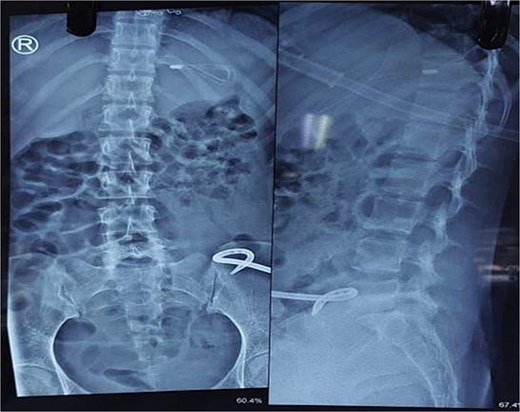

She was treated conservatively with IV fluids, analgesics, and antibiotics. Ultrasound-guided catheter drainage of the abscess yielded ~100 ml of pus. A post-procedure X-ray confirmed the position of the drainage catheter (Fig. 4). Anti-tuberculous therapy (ATT) was initiated under the DOTS strategy. Her obstruction resolved, and she was discharged on Day 4 with advice to continue ATT as per DOTS, a high-protein diet and follow-up in the surgery outpatient department. Orthopaedics consultation advised lumbar corset for ambulation support.

X-ray abdomen showing pig tail catheter in left inguinal region and nasogastric tube in stomach (anteroposterior and lateral).